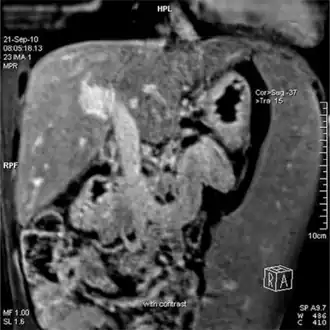

Magnetic resonance imaging of portal hypertension

Portal hypertension due to cirrhosis resulting in revascularization of the umbilical vein

Ultrasonography (US) is the first-line imaging technique for the diagnosis and follow-up of portal hypertension because it is non-invasive, low-cost and can be performed on-site.[12]

A dilated portal vein (diameter of greater than 13 or 15 mm) is a sign of portal hypertension, with a sensitivity estimated at 12.5% or 40%.[13] On Doppler ultrasonography, a slow velocity of <16 cm/s in addition to dilatation in the main portal vein are diagnostic of portal hypertension.[14] Other signs of portal hypertension on ultrasound include a portal flow mean velocity of less than 12 cm/s, porto–systemic collateral veins (patent paraumbilical vein, spleno–renal collaterals and dilated left and short gastric veins), splenomegaly and signs of cirrhosis (including nodularity of the liver surface).[12]